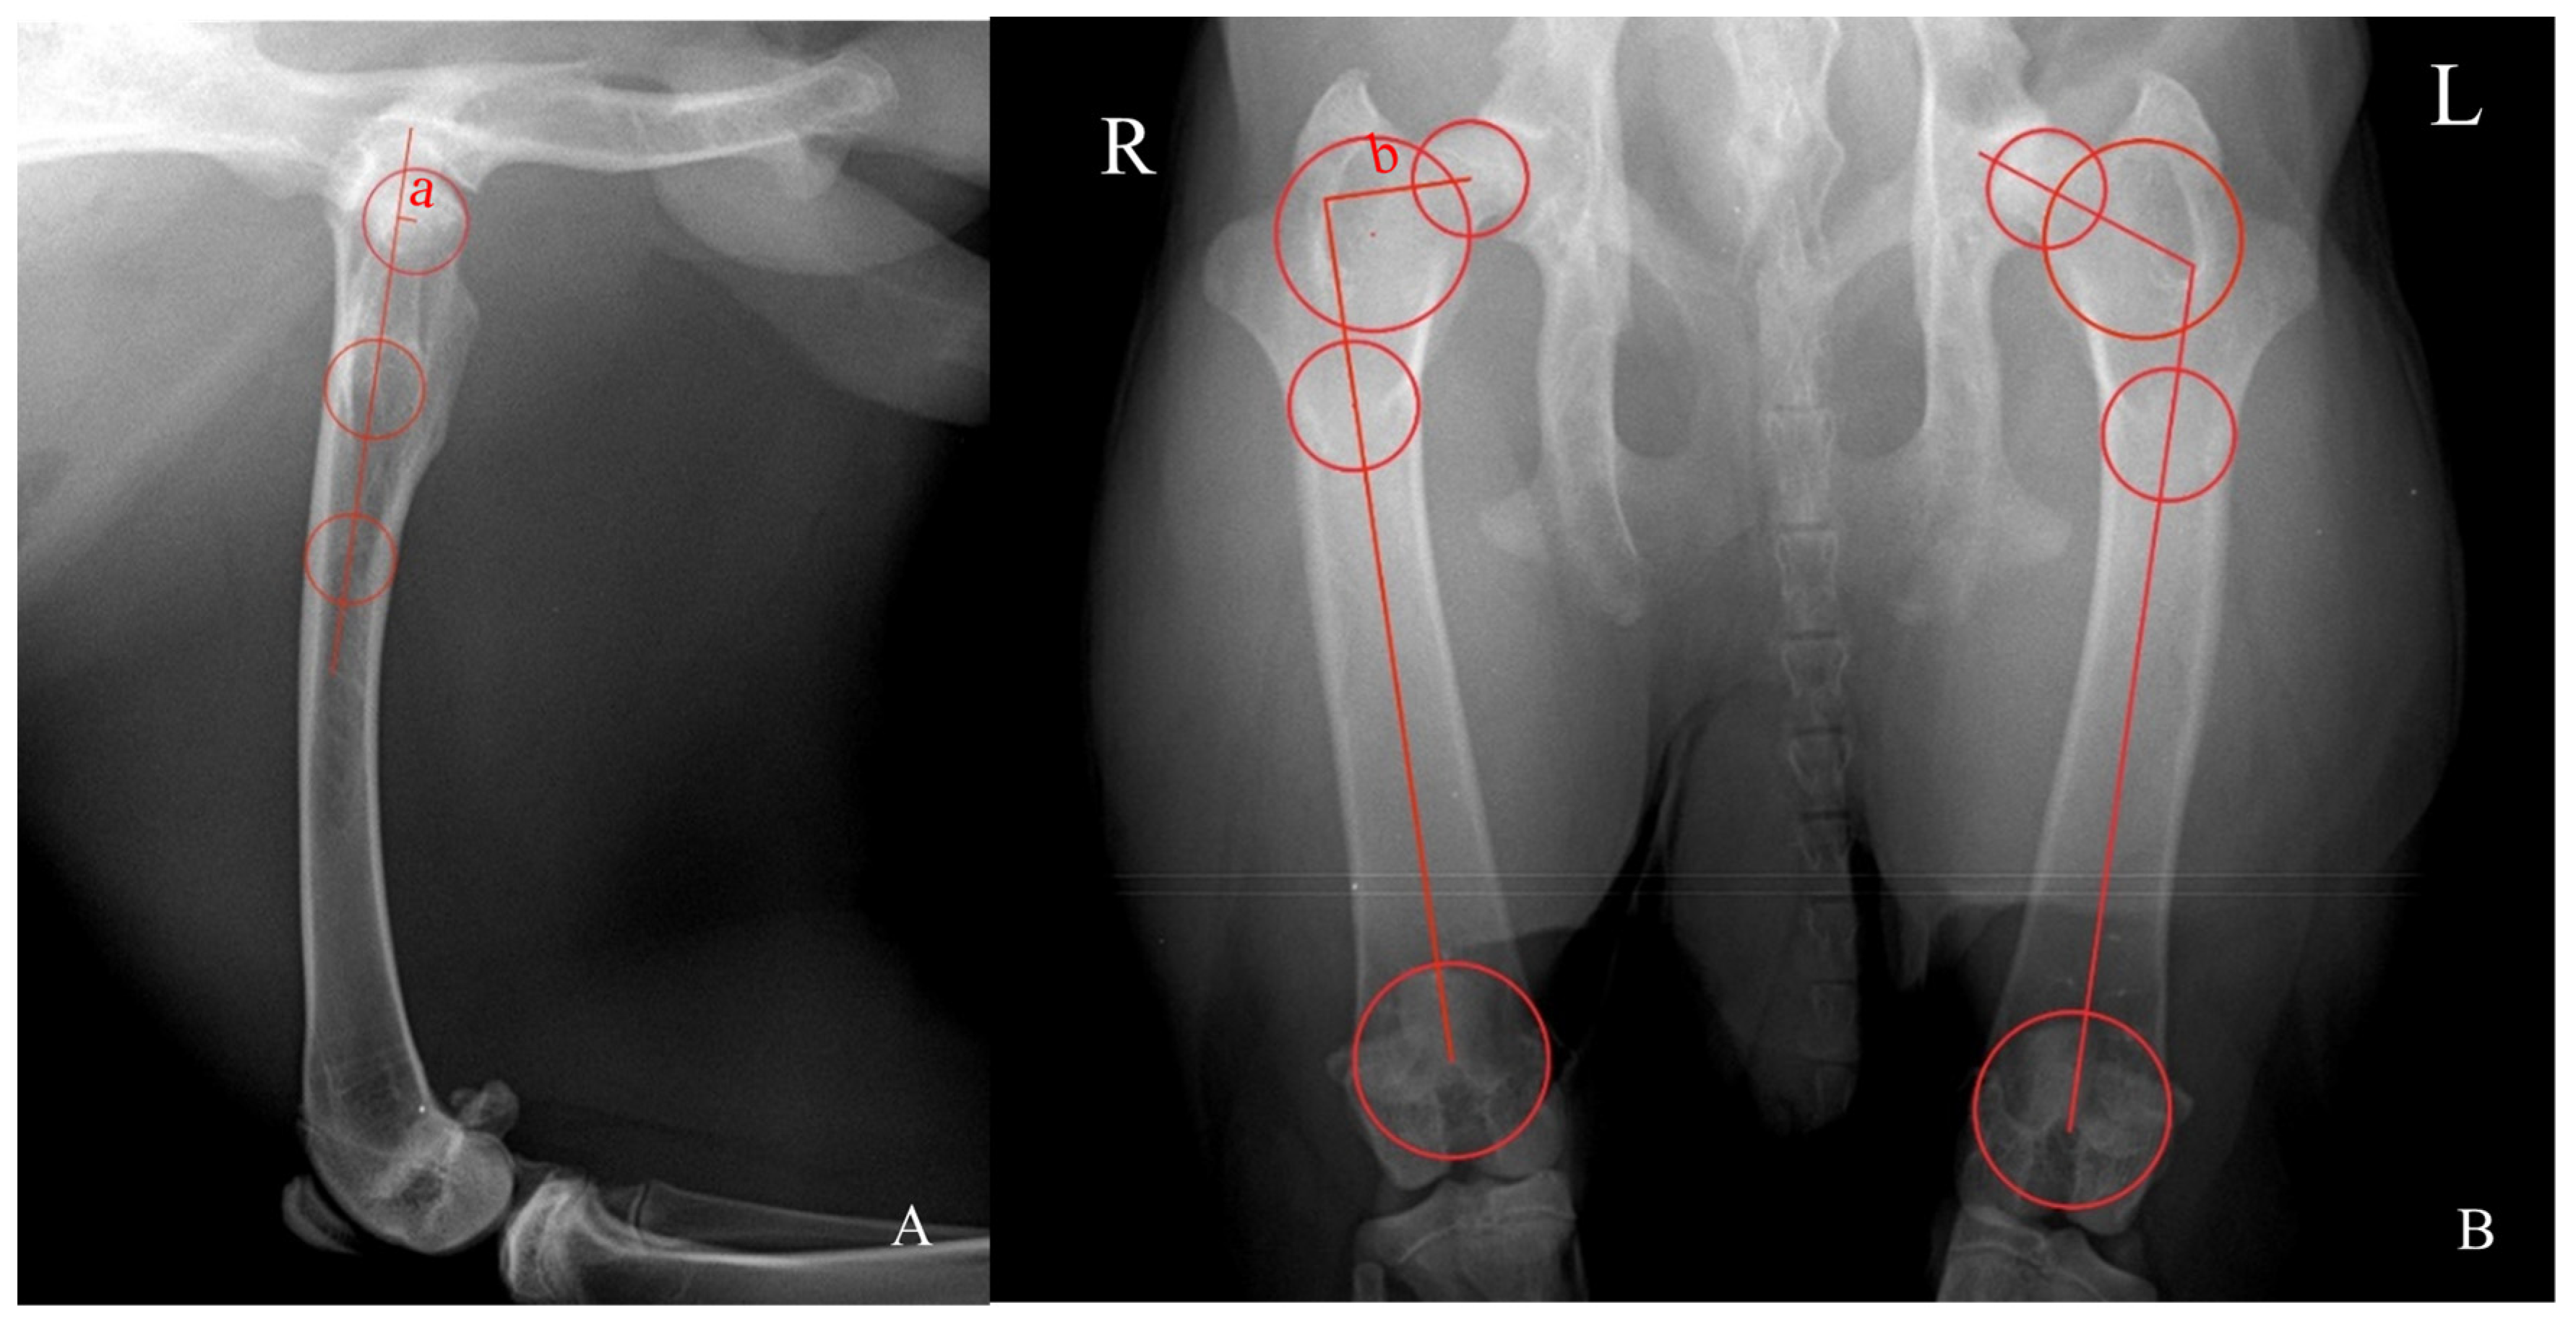

FAA was measured using the biplanar method (Reynold’s technique) and determined by the tangent of the distances ‘a’ and ‘b’ (tan (a/b), in mm) (Figure 1). Distance ‘a’ was assessed in the mediolateral radiograph and consists of the perpendicular distance between the center of the best-fit circumference drawn in the outer limit of the head of the femur and the axis of the proximal diaphysis of the femur defined by the center of the two best-fit circumferences at the most distal diaphysis between the greater and third trochanters and the most distal diaphysis of the proximal femur. Distance ‘b’ was measured in the ventrodorsal radiograph and entails the perpendicular distance between the center of the best-fit circumferences drawn in the outer limit of the head of the femur and between the greater and third trochanters and the femoral axis defined by the center of the two best-fit circumferences drawn between the most proximal and the most distal diaphysis of the femur [11,12]. FAI is the angle formed by the line connecting the center of the best-fit circumferences drawn at the head of the femur and between the greater and third trochanters and the line connecting the center of the best-fit circumferences at the most proximal and distal diaphysis border of the femur [11].

Figure 1. Illustration of the methodology used for assessing the anteversion (FAA) and inclination (FAI) angles of the head of the femur. (A) The mediolateral view of the hip joint. (B) The ventrodorsal view of the hip joint. R: right side. L: left side. FAA was determined by the tangent of the distances ‘a’ divided by ‘b’. Distance ‘a’ (A) consists of the perpendicular distance between the circumference’s center drawn at the head of the femur and the axis of the proximal femoral diaphysis defined by the circumferences’ center at the most distal diaphysis between the greater and third trochanters and the most distal diaphysis of the proximal femur. Distance ‘b’ (right side of (B)) entails the perpendicular distance between the circumferences’ center drawn in the head of the femur and between the greater and third trochanters and the femoral axis defined by the circumferences’ center drawn between the most proximal and the most distal diaphysis of the femur. FAI (left side of (B)) is the angle formed by the line connecting the circumferences’ center drawn at the head of the femur and between the greater and third trochanters and the line connecting the circumferences’ center at the most proximal and distal diaphysis border of the femur.